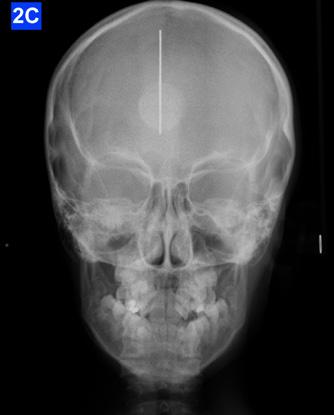

Lateral Cephalometric radiogram revealed a narrow airway in the tonsil area (5.0 mm), retrognathic maxilla and mandible (SNA - 78°, SNB - 76°), retrusive maxillary incisors (U1/SN - 91°), retrusive mandibular incisors (L1/GoM - 83°). She was Class III skeletally as ANB, Wits and the Harvold ∆ were – 2.4°, -5.0 mm and 24.8 mm The patient was hyper-divergent as seen from NS/GoM of40° and a Lower gonial angle of 79.7°. The patient was in CVMS 2 - 3 (Cervical Vertebrae Maturation Stage) (Figure 2-B) and an A-P Radiogram revealed a posterior crossbite (Figure 2-C).

Figure 2A: Pre-treatment, Panoramic radiogram Figure 2B: Pre-treatment, lateral Cephalometric radiogram

Figure 2C: Pre-treatment, AP Cephalometric radiogram